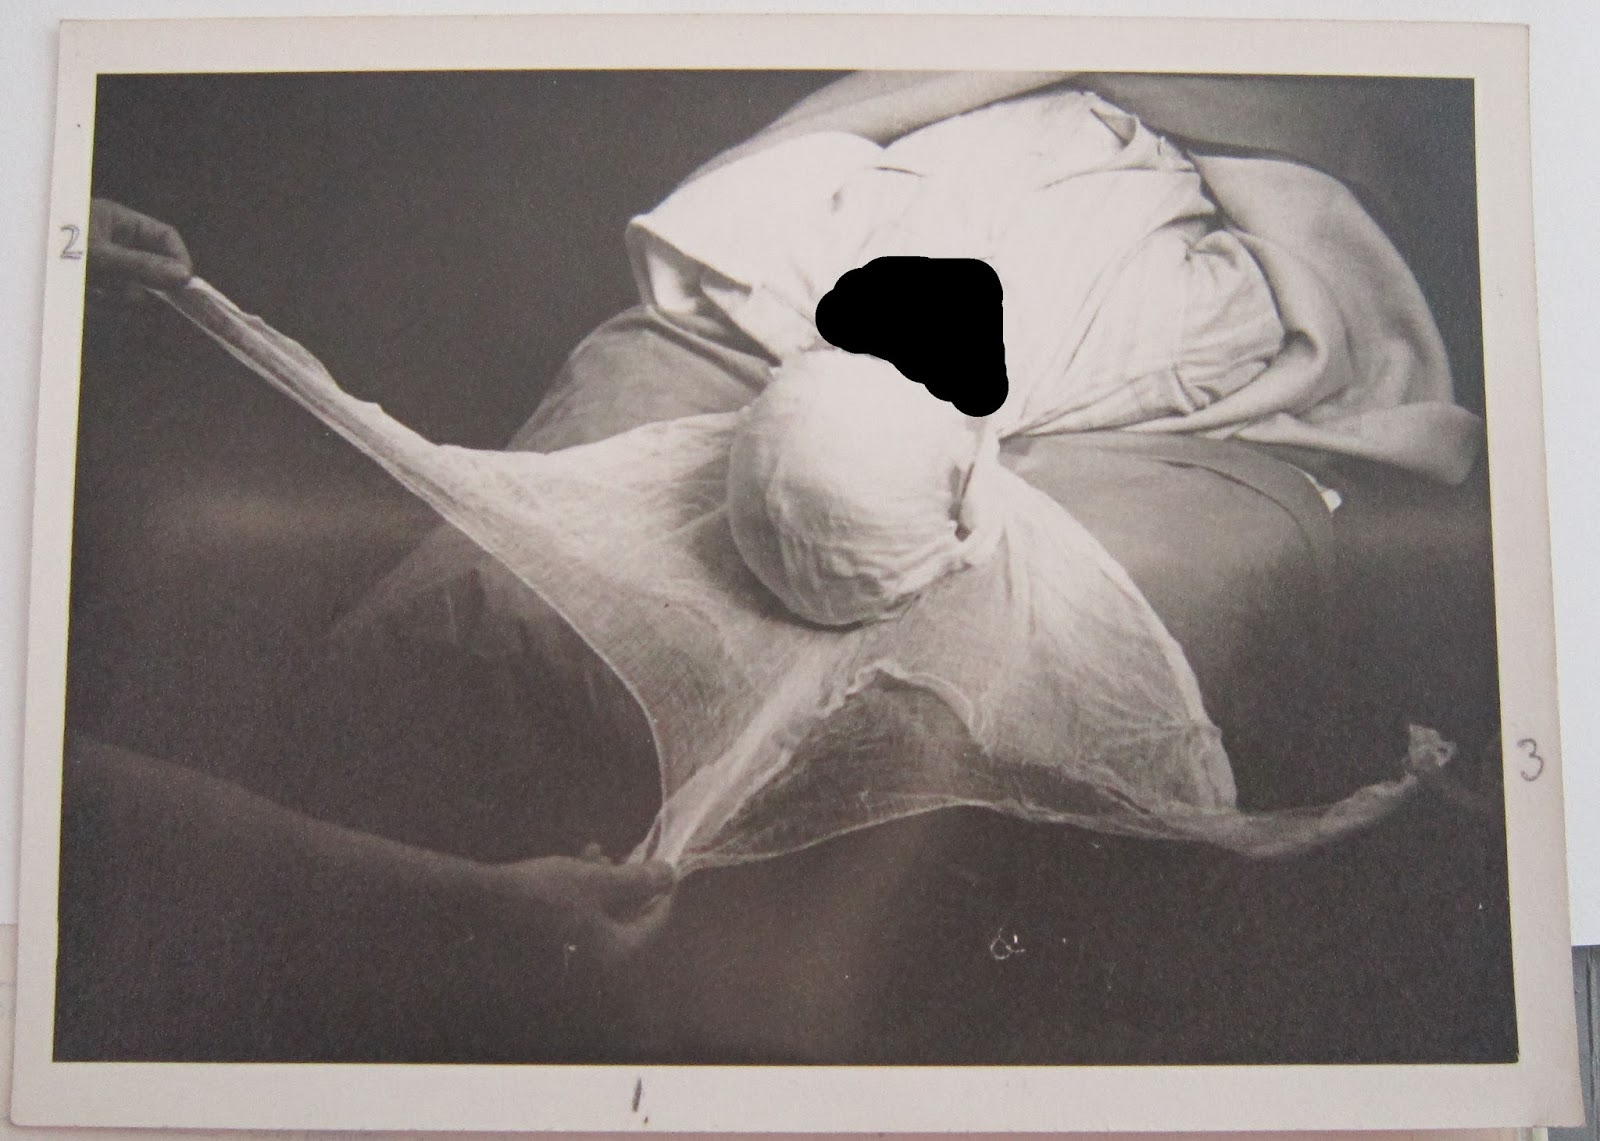

In 1947 he returned to Bangour to have this defect repaired. Rather than the bone graft mentioned in the letter, an acrylic plate was made to reconstruct his damaged skull. This process involved two operations, the first to take a cast and the second to fit an acrylic resin mould. Again, the patient recovered well and it was noted that, ‘the cosmetic result was very satisfactory’. These pictures show the patient’s wound being dressed after the operation, and are two of six found in the case file: